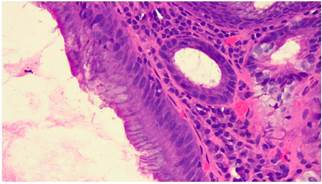

El estudio histopatológico reportó una mucosa esofágica comprometida por una lesión displásica, conformada por glándulas tubulares y vellosas, revestida por un epitelio cilíndrico simple, núcleos hipercromáticos sin evidencia de pérdida de la polaridad ni compromiso de la membrana basal. En la lámina propia se observó un infiltrado inflamatorio crónico en escasa cantidad, compatible con adenoma velloso, con displasia de bajo grado (Figuras 4 y 5).